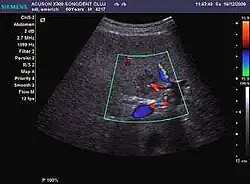

The ultrasound appearance is a well defined lesion, with very thin, almost unapparent walls, without circulatory signal at Doppler or CEUS investigation. The content is transonic suggesting fluid composition. The presence of membranes, abundant sediment or cysts inside is suggestive for parasitic, hydatid nature. Posterior from the lesion the acoustic enhancement phenomenon is seen, which strengthens the suspicion of fluid mass. They typically displace normal liver vessels but no vascular or biliary invasion occurs.

-

Liver cyst -